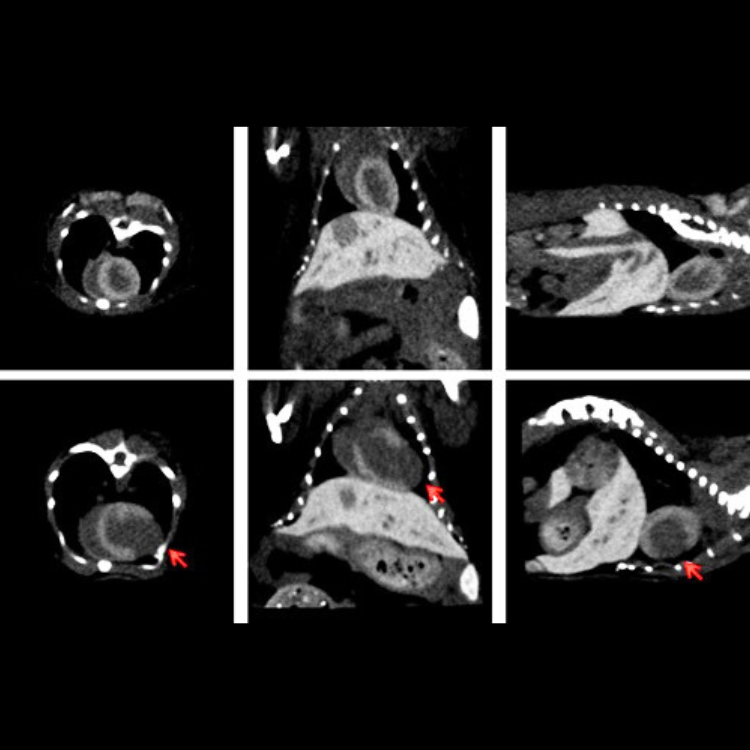

ExiTron MyoC 8000 is an innovative nanoparticulate agent optimized for CT studies of the myocardium. Its accumulation in healthy myocardial tissue as well as its high iodine concentration and long blood half-life enable visualization of pathological changes of the myocardium as well as functional cardiac imaging.

- Effectively visualize pathological changes of the myocardium, e.g. infarction

- Quantify infarct size

- Investigate functional cardiac parameters